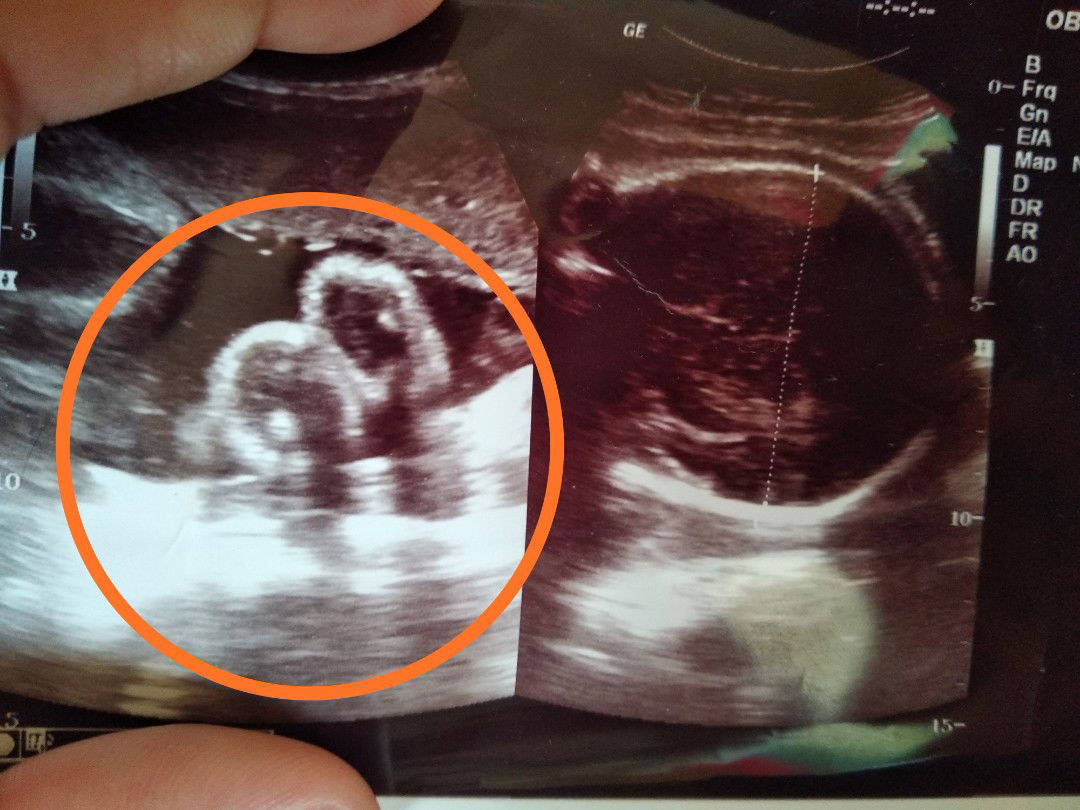

jenis kelamin cowo

Bunda bunda ,, waktu usia kandungan 7 bulan aku usg kata nya cewe ,,, pas sekarang usia kandungan 8 bulan dan ganti dokter , katanya jenis kelamin nya cowo ,, itu yang di bulatin katanya biji nya ini cowo ,, apa bener yah cowoo ,, apa bisa berubah lagi? Mau beli perlengkapan